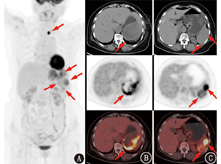

患者女,64岁,以"1周前体格检查发现脾脏占位"为主诉于本院就诊,病程中无发热、黄疸,无咳嗽、气喘、心悸、胸闷,无进行性体质量减轻,进食、睡眠、大小便正常。既往无手术、外伤史及其他肿瘤史,无结核、肝炎等传染病史。体格检查:无明显阳性体征。实验室检查:血常规、生化检测及肿瘤标志物指标均正常。颈部超声示:甲状腺左叶近峡部见12 mm×9 mm ×10 mm等回声结节,形态欠规则,局部欠清,内见不规则钙化灶。腹部CT平扫及增强CT示:脾脏见数个类圆形稍高密度影,较大者约92 mm×67 mm,内见片状低密度影,增强扫描呈相对低强化。结合相关检查仍无法确诊,遂行18F-脱氧葡萄糖(fluorodeoxyglucose, FDG)PET/CT(德国Siemens Biograph mCT)检查,显像(图1)示脾脏见多发类圆形混杂密度影,边界不清,较大者见不规则坏死,病灶较大者约8.8 cm×7.5 cm,糖代谢不均匀增高,最大标准摄取值(maximum standardized uptake value, SUVmax)9.1,考虑恶性病变可能性大;甲状腺左叶见类圆形稍低密度影,直径约1.4 cm,内见点状钙化灶,糖代谢异常增高,SUVmax 19.0。后行手术切除,术中探查发现脾脏上极占位约6 cm×5 cm,质地韧,与周围组织紧密粘连,肝脏无明显肝硬化改变,食管胃底部静脉无曲张,余脏器未见明显异常,遂行脾切除术+粘连松解术+冲洗引流术。术后病理检查(图2)示肿瘤细胞由席纹状排列的胖梭形细胞和多形性瘤细胞组成,多形性瘤细胞核大而不规则,染色质粗而深染;肿瘤内还可见多核瘤细胞,肿瘤内易见核分裂象,间质内可见慢性炎性反应细胞浸润。免疫组织化学:广谱细胞角蛋白(cytokeratin pan, CKpan;-)、上皮膜抗原(epithelial membrane antigen, EMA;-)、S-100蛋白(-)、CD34(+)、波形蛋白(vimentin;+++)、平滑肌肌动蛋白(-)、结蛋白(desmin;-)、CD68(+)、CD1a(-)、CD31(+)、CD21(-)、CD23(-)、P53(大部分为阴性)、细胞增殖核抗原Ki-67(阳性指数约为30%),符合恶性纤维组织细胞瘤(malignant fibrous histiocytoma, MFH)/未分化肉瘤。

目前并未发现可用于术前诊断脾MFH的特征性影像学表现。Makis等[2]报道了1例脾MFH肝转移的PET/CT显像,发现肝脾多发薄壁囊实性占位,坏死明显,边缘FDG代谢异常增高,脾脏最大病灶约9.6 cm×7.5 cm,SUVmax15.8。本例患者发现相对较早,未见远处转移,PET/CT显像与上述报道有不同之处,除了部分病灶见明显坏死,还有多处呈实性肿块,FDG代谢亦略低,因此,脾MFH影像学特点还需进一步总结。本例病灶光学显微镜下核分裂象多见,且免疫组织化学示细胞增殖核抗原Ki-67阳性指数约30%,提示肿瘤细胞增殖活跃,恶性程度高,与18F-FDG显像高摄取相符,而肿瘤的快速生长及炎性反应细胞的浸润可能是部分病灶出现囊变坏死的原因,从而在18F-FDG显像时呈现出缺损区。虽然本例18F-FDG显像无法做出确切的术前诊断,但可提示病变为脾脏原发恶性肿瘤,且无局部及远处转移,为临床准确分期、制定治疗方案提供了依据。